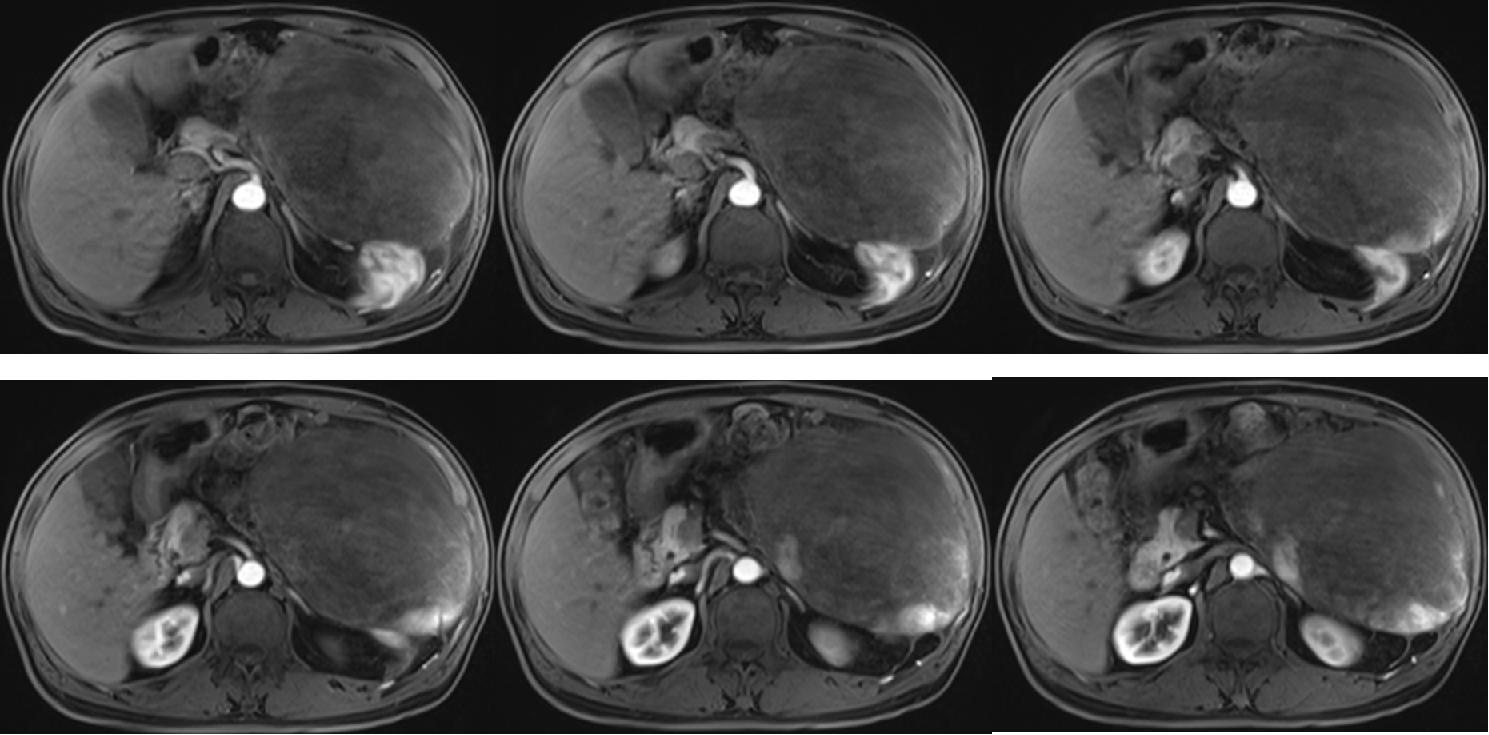

病例一

病史:男 73岁,主诉:查体发现腹腔占位半月余,高血压20年

左侧腹腔内脾肾间隙内见巨大等长T1 混杂长T2异常信号,其内信号欠均匀,增强扫描边缘及内部可见明显延迟强化,病变大小约为22.2x15.9x12.2cm,DWI与ADC 部分可见扩散受限,脾脏被向上推移,左肾被向下推压,病灶与胰腺分界尚可,胰腺被推压。动脉期可见左侧肋间动脉分支血管进入肿块。肝内见多发类圆形长T1长T2信号灶,增强扫描未见明显强化,大者截面约1.9x1.3cm。肝内外胆管未见明显扩张,90min 延迟期可见造影剂排泄双肾内见小类圆形无强化液性信号灶,未见明显强化,大者居右肾,直径约1.4cm,边界清双侧肾上腺显示尚可,未见明显异常信号。腹腔及腹膜后未见明显增大淋巴结。腹盆腔见液性信号。

左侧腹腔巨大占位性病变,符合肿瘤 MR 表现,间叶源性肿瘤不除外,请结合临床。